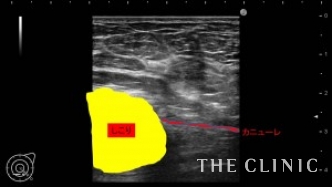

エコーにて、右にオイルシスト、左にオイルシストと4㎝の混合性腫瘤を認めました。(オイルシストの症例はNo.32でご紹介します)

混合性腫瘤の被膜が非常に硬く、中々カニューレが被膜を破れませんでした。何とか突き破ることが出来、ベイザーリポで崩していきます。